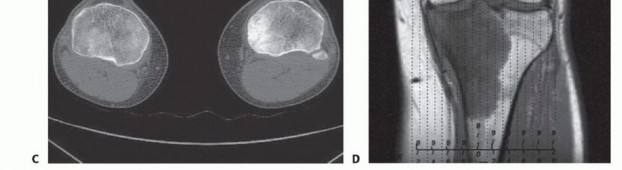

- التصوير بالرنين المغناطيسي (MRI): يُعتبر الأداة الأكثر أهمية لتحديد مدى انتشار الورم داخل العظم، وفي الأنسجة الرخوة المحيطة، وعلاقته بالأوعية الدموية والأعصاب. يُساعد في تحديد هوامش الاستئصال الجراحي.

- التصوير المقطعي المحوسب (CT Scan): يُستخدم لتقييم التدمير العظمي بشكل أفضل، وتحديد وجود أي نقائل في الرئتين أو أجزاء أخرى من الجسم.